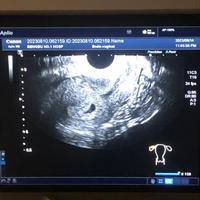

胎儿性别鉴定是利用现代医学技术对胎儿进行性别的确认。常用的鉴定方法有B超检查、羊水穿刺、绒毛取样、胎盘组织取样等。这些方法虽然可以精准地确定胎儿性别,但也存在一定的风险,如感染、出血等。B超是最为安全、简便和可靠的方法。在孕妇怀孕满20周时,进行B超检查可以清晰地了解胎儿的性别。在B超检查前要遵循医生的指导,做好准备工作,如憋尿、空腹检查等。同时,B超检查不仅可以确定胎儿性别,还可以检查胎儿的各项指标,包括体重、发育水平等。